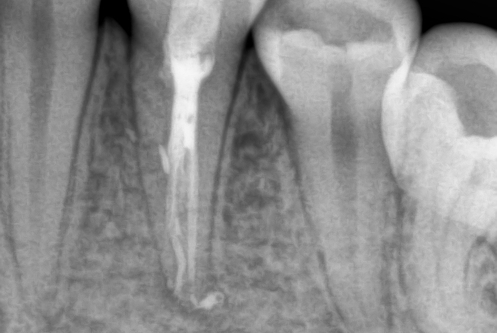

В стоматологической клинике "5 Принципов" в Симферополе мы гордимся тем, что каждый пациент получает индивидуальный подход и безупречный результат в области эндодонтического лечения под микроскопом. Наши специалисты применяют современные цифровые технологии, микропроцессорные и нейромодуляционные инструменты, что позволяет достичь максимальной точности и минимального дискомфорта. В портфолио клиники — широкий спектр кейсов: от первичной диагностики пульпита до сложной ретенированной резорбции и повторной эндодонтии. Мы беремся за зубы любых степеней сложности: от моляра до резцов, используя щадящие концевые инструменты и безболезненные методы постоянной анестезии. Все процедуры проходят под увеличением, что обеспечивает точное удаление инфицированной ткани и сохранение естественной анатомии зуба.Особое внимание мы уделяем постпроцедурному наблюдению: контроль за герметичностью заполнения корневых каналов, профилактические рекомендации и возможная корректировка плана лечения при необходимости. В "5 Принципах" мы разумно сочетаем комфорт, эстетическую привлекательность и долгосрочную функциональность. Результат — здоровые зубы, уверенная улыбка и спокойствие наших пациентов в Симферополе. Запишитесь на консультацию и убедитесь сами в нашем подходе к качественному эндодонтическому лечению.